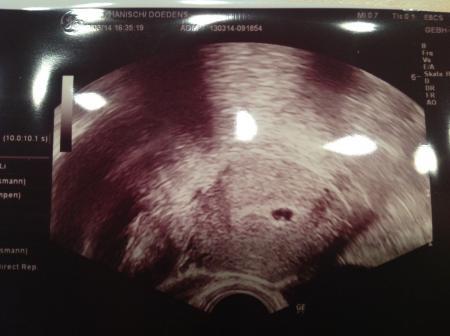

Das ist mein US von heute!

Bild zu

Laut meinem FAbin ich schwanger! Wir müssen nun noch bis morgen warten, ob sich der hCg wert erhöht hat. Mir wurde nämlich nochmal Blut abgenommen. Und im US ist diesmal mehr wie gestern zu sehen gewesen. Gestern meinte der FA noch, es sei nur Flüßigkeit. heute sind schon Fruchthülle und Zellkern zu sehen Nun heißt es nochmals warten und hoffen das mein HCG steigt Wir sind ganz aufgeregt! Und der FA aus'm Kiwu meinte noch zur iui, das Sperma meines Mannes sei noch schlechter wie sonst (Oat3) und dies sei dann nur eine Probeinsemination. Allein deswegen kann ich es noch gar nicht fassen! Drückt mir die Daumen! Ich möchte mich jetzt noch nicht so richtig freuen! Hab bissl angst vor morgen! Ahhhhhhhhhhhh

Wow, das gibts ja gar nicht! Bin begeistert... Dass man sooo früh schon was sieht. Wahnsinn :) Das lag an meinem fleißigen Daumendrücken :D Ich will auch...